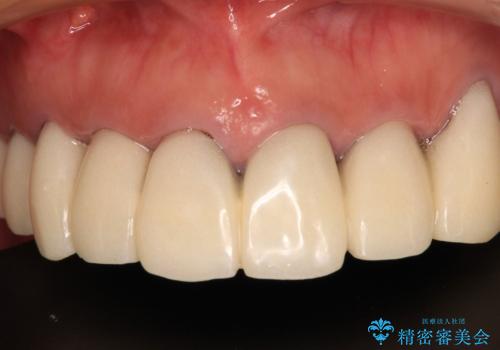

仮歯で咬み合わせの調整を行ってからは、特に不安定になることもなく、非常にスムーズに治療を進めて行くことができました。

前歯奥歯ともに望ましくない力がかかりやすい咬み合わせであるため、就寝時にはマウスピースを使用するようにお伝えしております。